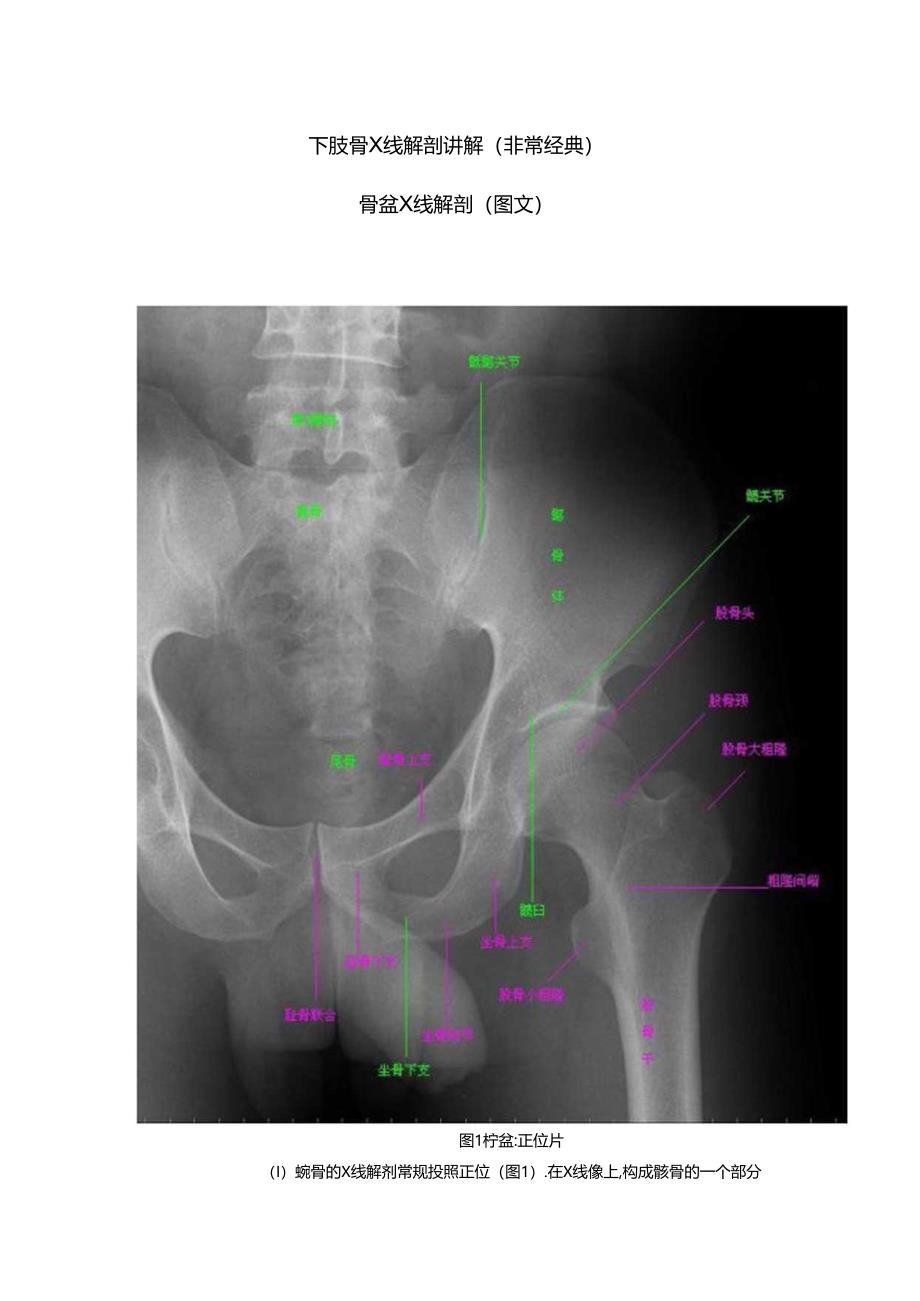

1、下肢骨X线解剖讲解(非常经典)骨盆X线解剖(图文)图1柠盆:正位片(I)蜿骨的X线解剂常规投照正位(图1).在X线像上,构成骸骨的一个部分融合于靛臼,可清晰辨别。骼骨翼的内侧1/4影像与IK骨影像重叠,外侧3/4因有船窝而较透亮。鹿崎阴影较致密,边缘不光滑,外侧可见微前上就影,微后上就则重福手般骨影内,弓状线及什盆腔内侧壁形成豆合影像,外侧可见弧形的胱臼阴影。髅臼阴影的上段粗而致密,中段较细,它向下绕过微臼切迹前部的下缘,与耻骨体的内面形成条“U”形的致密线,称为泪滴线(KOCkIa泪滴),泪滴线二脚之间的距离,即眈臼窝的厚度。股臼内卜方的透亮影为闭孔。闭孔账的上界是耻骨上支、外侧界是坐骨体的

2、卜.份,酸钟结节阴影与其中段.坐骨棘的阴影型三角形突向盆腔.(2)骨盆的X线解剖骨盆一般投照前后位,检查附、尾料时可加照醐位,检查怅期关节时应加照45斜位,产科骨盆测量另仃其特殊投照措施。骨盆前后位片上.艇骨中线应通过耻料联合。瓶酩关节左右对称,关节间隙下半部分可以显示,上半部常投影出模糊双线影。界线的影像在女性呈卵圆形,在男性略呈鸡心形。骼崎连线影恰好通过第4、5腰椎间隙。由解靖影向外可追踪到骼前上、下林,由酷前下棘到股骨颈外上缘的连线称能颈线,用以鉴定假关节与否正常。正位片上,可以测量耻骨卜.角,男性为税角,女性为钝角。女性竹盆径线的测量,可以采用正位(见图I)和侧位。正位片上,界线影像最

3、远点连线为入口横径,正常为12.3cm;两侧坐骨棘连线为中骨盆横径,正常为10.5cm:两侧坐骨结节间即为小骨盆出口横径,正常为1.1.8cm,例位片上,耻骨联合后修上端到饰骨岬连线为小骨盆入口前后径,正常为11.6cm:耻骨联合后缘卜端和坐骨棘中点的连线延长到舐骨的前绥,为中骨盆前后径,正常12.2cm;耻骨联合后下缘到耀尾关节的连线,为小骨盆出口前后径,正常11.8cm。(3)版关节.的X线解剖常规拍摄正位(见图1)和恻位X线片。正位线片上,因隧臼:骨之间以“Y”形软骨相连,融合之前,体现为横行带状透亮影,其宽窄伴随年龄变化而变化。年龄越小此透亮带越宽:年龄越大,透亮带变窄,1517岁左右